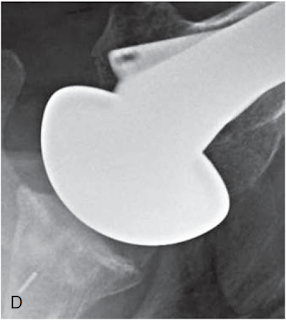

Signs of subscapularis failure in include excessive passive external rotation

and weakness of the belly press

and sometimes anterior instability.